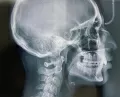

У меня нижняя челюсть на пару миллиметров больше выпирает, чем верхняя, и при смыкании челюстей, нижняя челюсть сдвигается немного вправо.

Без расчета ТРГ снимка в боковой проекции, ответить на сто процентов, необходима ли Вам операция, не представляется возможным.

Возможно закамуфлировать Вашу ситуацию, т.е. нижние зубы немного наклонить кзади, а верхние вперед, но, возможно, Ваш подбородок будет выступать вперед.